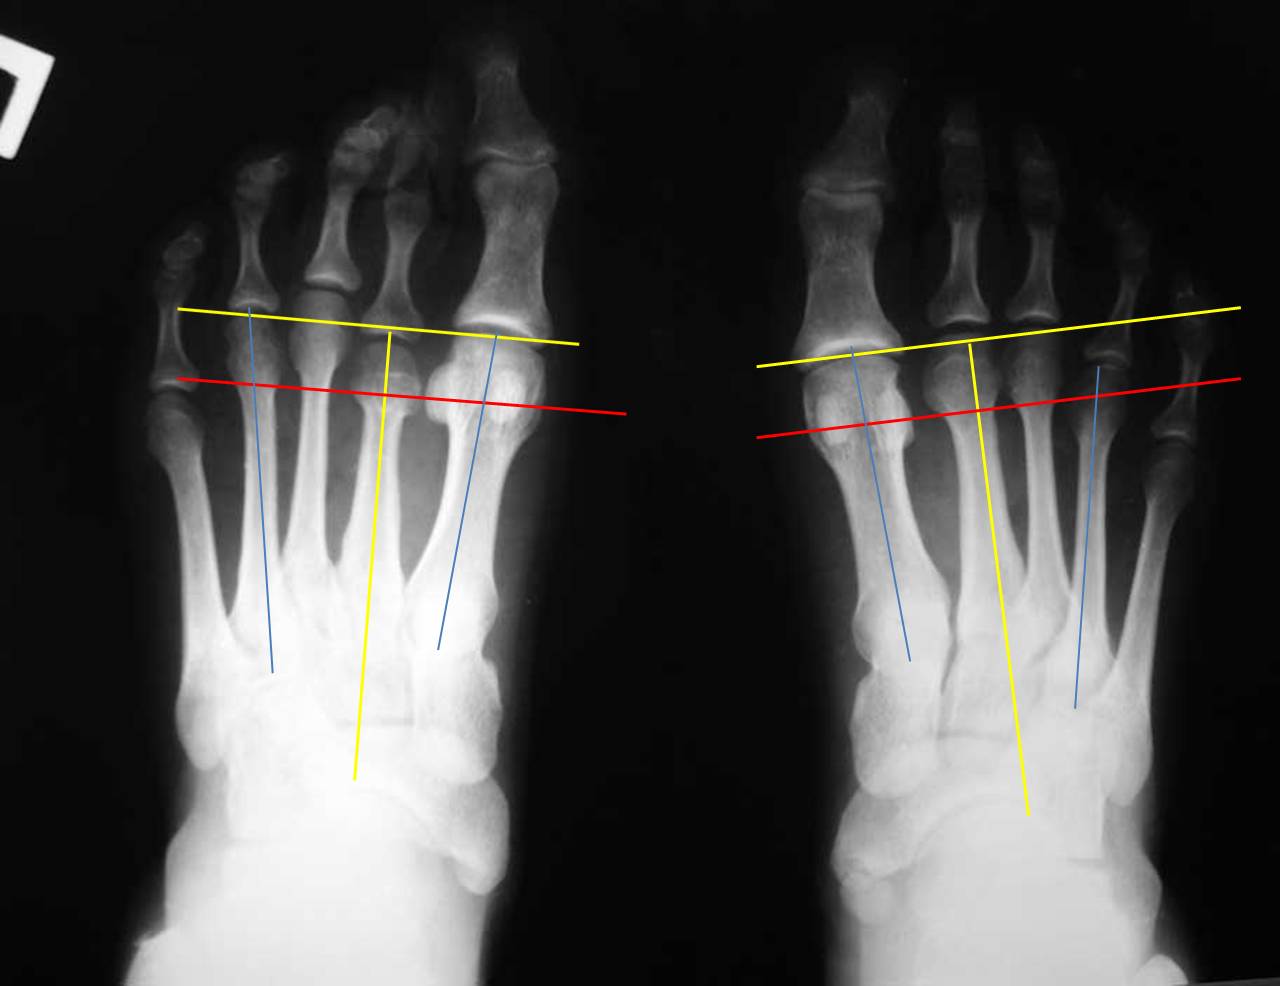

Я провел несколько ориентиров на представленных рентгенограммах, чтобы показать разницу в биомеханических ситуациях. На левой стопе перпендикуляр, проведенный к оси 2 плюсневой кости через дистальный конец 1 плюсневой (желтые линии) (принято за ориентир брать ось 2 плюсневой кости) проходит через верхушки 2 и 3 плюсневых. В нормальной ситуации 2 плюсневая кость должна быть чуть длинее 1-й. То есть на левой стопе можно говорить об относительно длинной 1 плюсневой кости. Именно этим объясняется наличие у молодой женщины признаков артроза 1 плюснефалангового сустава. А вот длина 4 плюсневой кости на левой стопе нормальная: перпендикуляр к оси 2 плюсневой проходит через середину латеральной сесамовидной кости и середину головки 4 плюсневой (красная линия). Теперь посмотрите на правую стопу: 3-я плюсневая кость намного длинее 1-й, а 4-я такой же длины. Такого в норме никак не может быть. А вот вторая при правильной разметке оказывается совсем чуть чуть короче первой. При этом абсолютная длина 1-й плюсневой (в милиметрах) у меня получилась на левой стопе даже больше, а длина 4 плюсневой на правой стопе на 4мм больше, чем на левой (голубые линии). Вот и получается, что на правой стопе наряду с небольшим укорочением 2 плюсневой есть более значимое относительное удлинение 3 и 4 плюсневых. И это в перспективе может быть причиной центральной метатарсалгии. Но пока жалобы пациентки связаны только с молоткообразной деформацией 2 пальца, лечение должно быть направлено на ее устранение наименее травматичным способом.

Лучше, когда на все равномерно. Но у данной больной удлинены 3 и 4 плюсневые. И значит на них, возможно, приходится избыточная нагрузка. К тому же еще раз обращаю Ваше внимание на толщину диафиза 2 плюсневой, которая свидетельствует о ее функциональной перегрузке. Возможно, ее головка расположена ниже остальных. Оценить расположение головок по переднезадним рентгенограммам мы не можем.

Я не зря задал такой вопрос о НОРМЕ именно для конкретной больной. Хотя, как Вы правильно подметили, я не очень знаком «с понятием формулы, или взаимоотношений длин плюсневых костей, которые определяют равномерность нагрузки на передний отдел стопы», но я знаю, что существует три типа взаимоотношений длин плюсневых костей на НОРМАЛЬНОЙ стопе: index minus type, index plus-minus type and index plus type (H. T. Kim, S. H. Lee, C. I. Yoo, J. H. Kang, J. T. Suh. The management of brachymetatarsia//J Bone Joint Surg [Br] 2003;85-B:683-90). В этой же статье и рисунок 2 есть, посмотрите эти типы НОРМЫ. Поэтому то, что Вы нарисовали ( отношение 1 и 2 плюсневых костей на левой стопе) является нормой, а Вы утверждали обратное. Поэтому я считаю, что для данной конкретной больной взаимоотношение плюсневых костей является НОРМОЙ, от чего и надо отталкиваться при сравнении длины плюсневых костей на обеих стопах. Да, я с Вами согласен, что по сравнению с левой стопой на правой удлинены 3-5 плюсневые кости на 2-3 мм, что не считается патологией. Равномерное и незначительное удлинение плюсневых костей (на 2-3 мм) не является патологией. Вы со мной согласны? Да, головка 5 плюсневой кости по отношению к головке 4 плюсневой кости на левой стопе на 2-3 мм стоит выше, чем на правой. Головка 4 плюсневой кости по отношению к 3-й плюсневой кости на левой стопе стоит на 3 мм выше, чем на правой. НО, САМОЕ ГЛАВНОЕ – головка 3 плюсневой кости по отношению к головке 2 плюсневой кости на левой ( нормальной) стопе стоит где-то на 3-4 мм выше головки 2 плюсневой кости, а на правой ( больной) стопе головка 3 плюсневой кости по отношению к головке 2 плюсневой кости стоит выше АЖ на 17 мм. Это Вы считаете НОРМОЙ? Это, по-Вашему, не считается брахиметатарсией? Brachymetatarsia is diagnosed when one metatarsal ends 5 mm or more proximal to the parabolic arc(H. T. Kim, S. H. Lee, C. I. Yoo, J. H. Kang, J. T. Suh. The management of brachymetatarsia//J Bone Joint Surg [Br] 2003;85-B:683-90). А в нашем случае разница АЖ в 13-14 мм по сравнению с плюсневой формулой на левой-нормальной стопе.

Теперь об укорочении 1 пальца. Вы же сами вполне справедливо отметили, что даже в абсолютной величине на левой стопе 1 плюсневая кость длиннее подобной же кости на правой – больной стопе. Плюс ко всему, на Вашем, профессионально расчерченном рисунке, можно четко увидеть, что расстояние между головками 1 и 3 плюсневых костей на левой стопе – 0 мм, а на правой-больной стопе – МЕНЬШЕ АЖ на10 мм. То есть 1 плюсневая кость на больной стопе по отношению к нормальной параболе плюсневых костей УКОРОЧЕНА. О чем я и говорил, а Вы почему-то возражали.